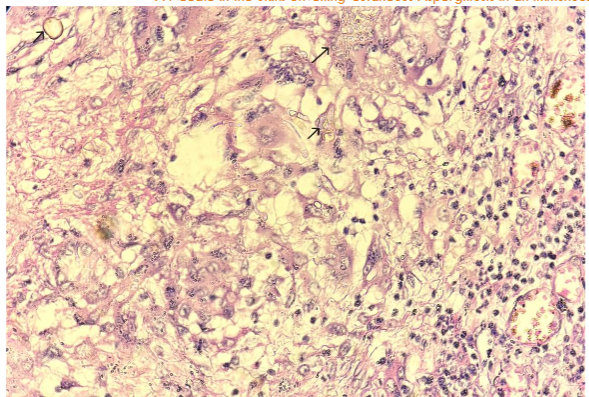

PAS Stain in cytology smears also confirmed the same. Excision biopsy was done and histopathology sections showed an unremarkable epidermis with deep dermis showing organised collections of neutrophils with necrotic centre and multiple septate fungal hyphae with acute angle branching. Spores were also noted. PAS and GMS staining was done and confirmed the presence of fungal elements.

Narrow septate hyphae with acute-angle branching is seen in tissue sections of our case, particularly when special stains are used (PAS and GMS). In our case, cytological examination is pivotal in identifying Aspergillus species, followed by biopsy with fungal stains confirmed the diagnosis.